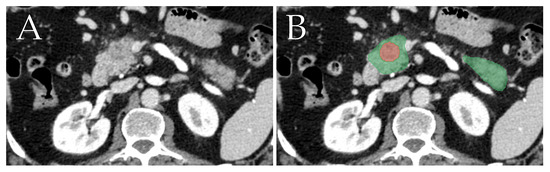

We trained the nnU-Net to segment the pancreas and tumors by using the 282 training samples provided by MSD. Then, the inference was ran on our dataset, and the produced pancreas-tumor masks were saved to be used for feature extraction. Figure 3 depicts an example of a segmentation result on a single image slice.

Figure 3. Example showcasing the segmentation of pancreatic ductal adenocarcinoma (red) and the rest of the pancreas (green). Image (A) depicts the original image, and image (B) depicts the image with the segmentations overlaid on top.